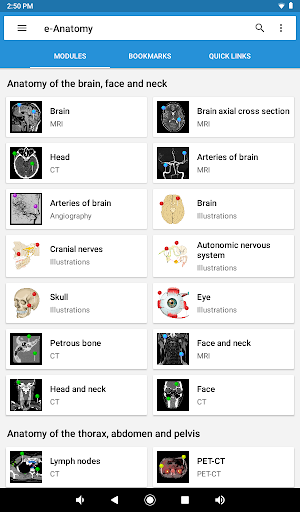

New : You can now filter the modules by region or by content type so you can find the module you are looking for much faster.

-Two new modules : Brain - TOF and Brain Angiography, Atlas of normal neurovascular anatomy of arteries of the brain on a cerebral angiogaphy.-The interface has been reworked.-A new tab named "QuickLinks" is available, dispatching modules in sections of the human body and allowing you to fast travel to the modules you are looking for.-Fixed small bugs.